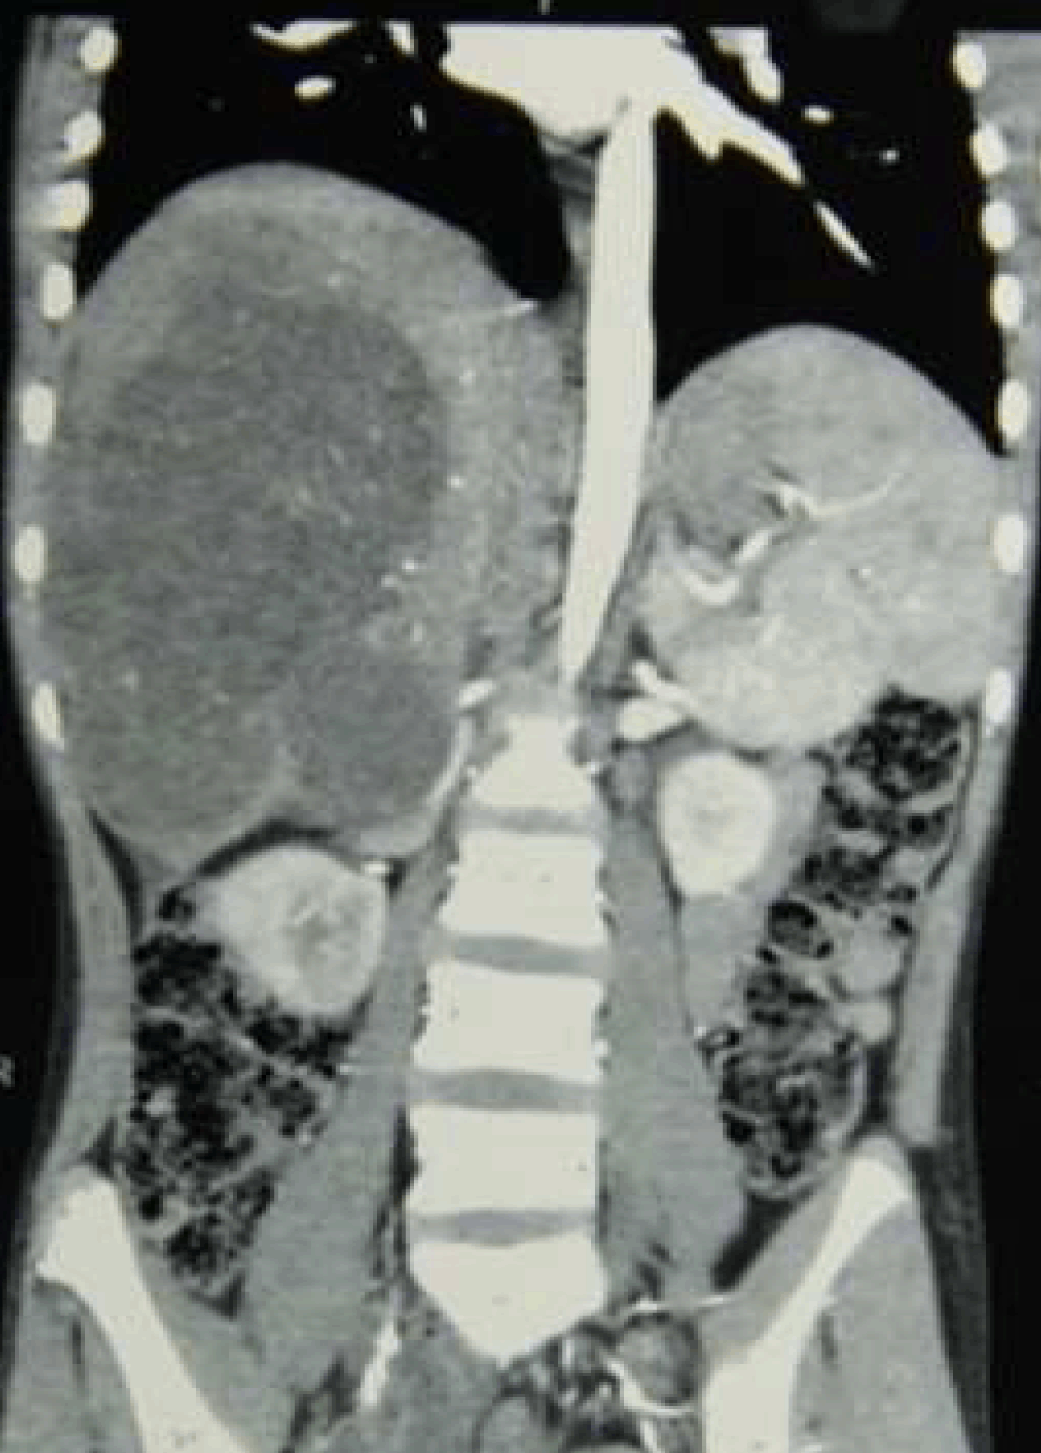

A 16-year-old boy with body weight of 26 kg was presented to us with a mass in the right hypochondrium since one month with history of abdominal pain, fever with chills and rigors. He had no history of jaundice, weight loss or loss of appetite. On elaborating the history, the mass was present for the last one month and rapidly increased for the last one week with severe intolerable pain last four days. On clinical examination, abdomen was soft and minimal guarding was present. A firm tender hepatomegaly was present 6 cm below right costal margin. Surface found to be smooth and edges were rounded. Contrast-enhanced computed tomography scan of abdomen revealed 15x11x9 cm heterogeneous multi-septated lobulated mass lesion involving right lobe of liver involving the segments 5, 6, 7, 8 (Figure 1) and (Figure 2). Portal venous Doppler study showed displaced and stretched right portal vein with normal flow. Laboratory investigations at the time of admission showed hemoglobin 8 g/dL, platelets 4 lakhs/mm3, blood sugar 80 mg/dL, blood urea 22 mg/dL and serum creatinine 0.8 mg/dL. Two units of packed cells were transfused and the preoperative hemoglobin was 10 mg/dl. Tumor markers AFP and CA 19-9 were done. Alpha fetoprotein value was 4 ng/mL and CA 19–9 was found to 20 U/mL. Liver biopsy was not taken to avoid the risk of seedling of an operable tumor.

Figure 1: Contrast-enhanced computed tomography scan of abdomen showing heterogenous mass lesion in right lobe of liver.

Figure 2: Coronal view of contrast-enhanced computed tomography scan of abdomen showing the lesion occupying the entire right lobe.